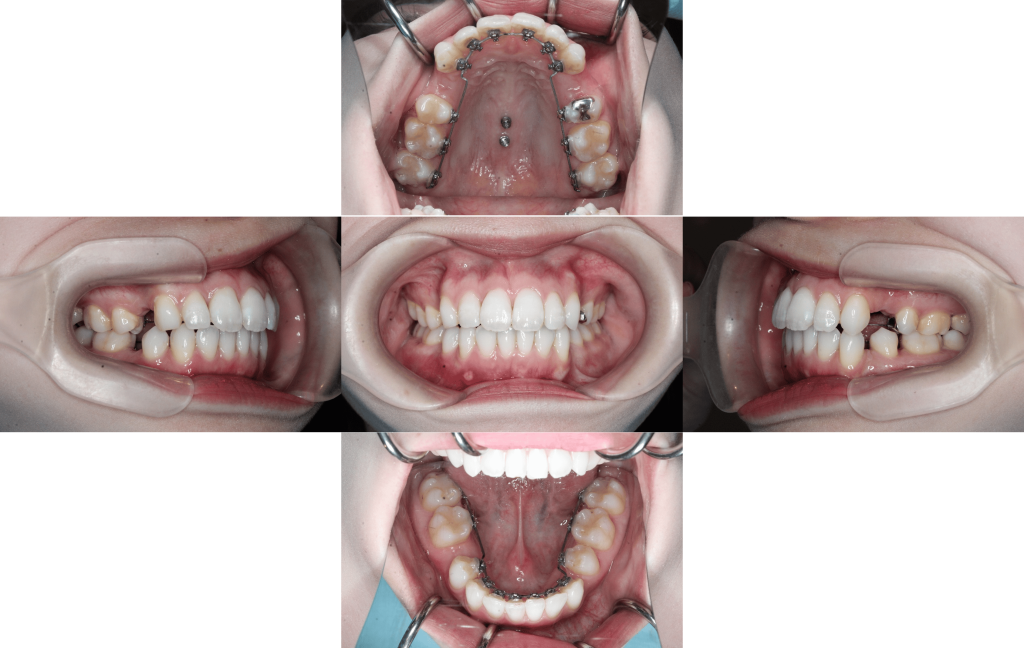

約6か月経過